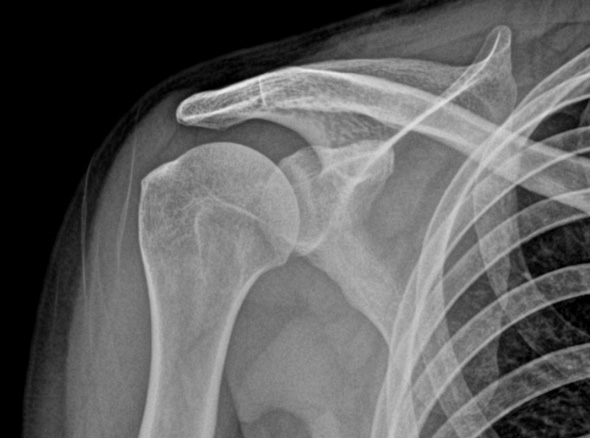

오십견은 어깨를 감싸고 있는 관절 조직인 관절낭에 염증이 발생하면서

유착되어 어깨의 움직임이 제한되고 통증이 유발되는 질환입니다.

가벼운 외상이나 혹은 회전근개 질환 등

여러가지 어깨 질환이 동반되어 나타나게 됩니다.

3-6개월 이상 보존적 치료를 하였으나 호전이 없는 경우

당뇨가 있는 경우

동반된 병변이 있는 경우 (석회, 충돌증후군, 회전근개 파열 등)

운동 범위의 감소가 매우 큰 경우